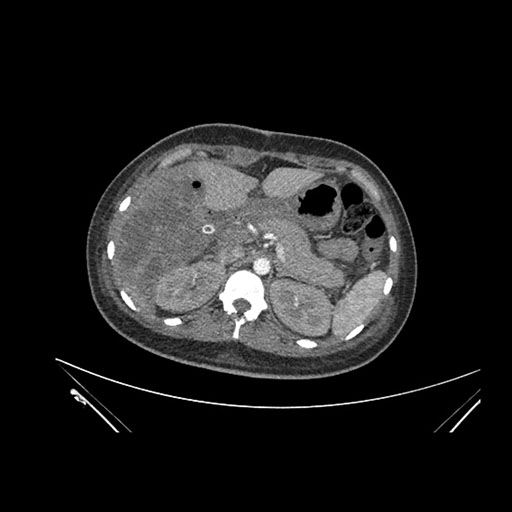

Axial Arterial